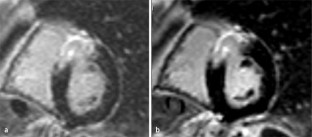

Abb. 2

31. Strach K, Meyer C, Thomas D et al (2007) High-resolution myocardial perfusion imaging at 3 T: comparison to 1.5 T in healthy volunteers. Eur Radiol 17(7):1829–1835

CAS  PubMed  Article  Google Scholar